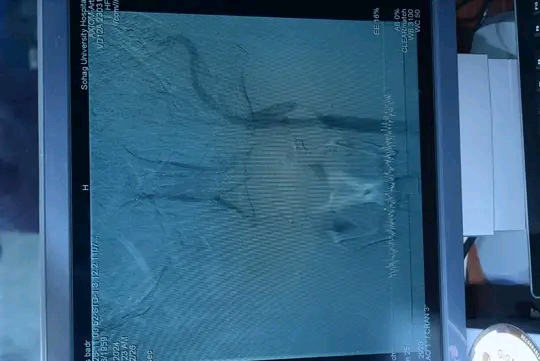

وفى السياق ذاته، أشار الدكتور أحمد كمال، المدير التنفيذي للمستشفيات الجامعية، إلى أن وحدة القسطرة المخية استقبلت خلال الشهر الماضى ٦ حالات طارئة، تراوحت أعمارهم بين ٢٠ و٤٥ عامًا، حيث تم إجراء عمليات دقيقة بإستخدام تقنية القسطرة المخية، مما ساهم في إنقاذ حياتهم وتقليل المضاعفات الناتجة عن السكتات الدماغية وتمدد الأوعية الدموية المخية والوحمات الشريانية بالمخ.

ووجه الدكتور عابدين خيرالله قاسم رئيس قسم جراحة المخ والأعصاب شكره وتقديره لإدارة الجامعة بقيادة الدكتور حسان النعماني علي دعم الوحدة، موضحًا أن القسطرة المخية تُعد من أحدث التقنيات العالمية المستخدمة في علاج السكتات الدماغية وتمدد الأوعية الدموية المخية، حيث تتيح للأطباء التدخل العلاجى دون الحاجة إلى جراحة تقليدية، من خلال إزالة الجلطات وإصلاح التمددات الشريانية بإستخدام الدعامات والملفات الحلزونية، مما يسهم فى تحسين فرص التعافى السريع وتقليل معدلات الإعاقة الناتجة عن الجلطات الدماغية.